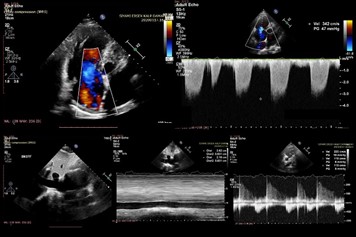

Sağ kalp boyut ve fonksiyonlarını değerlendirdiğimizde sağ ventrikül çaplarının oldukça genişlemiş olduğu (60*50*79 mm). Sağ ventrikül fonksiyonlarını temsil eden TAPSE ve RVS normal sınırlarda idi. Sağ ventrikül strain değeri ise -%18.2 olarak normalin (-%20) bir miktar altında olduğu tespit edildi (Resim-3).

Resim-3

Orta- ileri triküspit yetmezlik jeti üzerinden hesaplanan pulmoner arter basıncı inspiratuar kollapsı kaybolmuş ve dilate inferior vena cava göz önünde bulundurulduğunda artmış sağ atriyum basıncı eklendiğinde 60 mmHg olarak hesaplandı (Resim-4).

Resim-4: